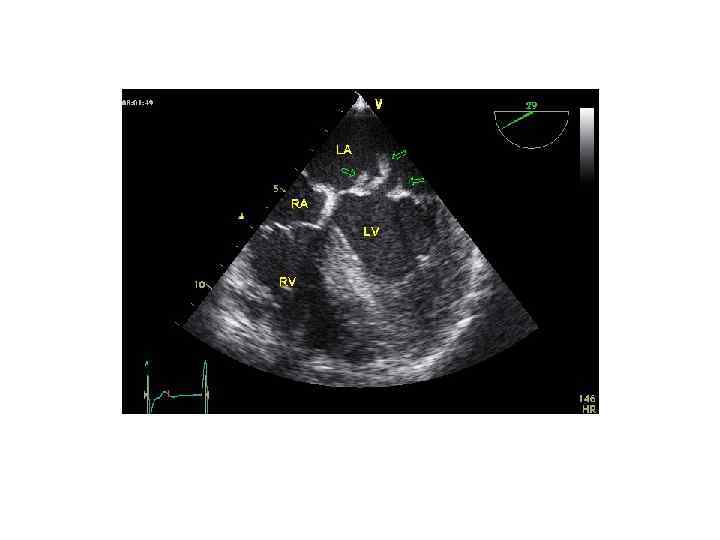

Эхо. КГ при субклинической ревматической болезни сердца

Выраженная регургитация при субклинической ревматической болезни сердца (критерии ВОЗ)

Эхо. КГ критерии субклинического ревматического поражения сердца Допплерографические (критерии ВОЗ 2001): • Поток регургитации > 1 см длиной • Поток регургитации как минимум в двух проекциях • Мозаичный цветной поток с пиковой скоростью >2, 5 м/с • Поток сохраняется на протяжении всей систолы (митральный клапан) или диастолы (аортальный клапан) Комбинированные пересмотренные критерии: Допплерографические признаки: • Регургитация любой степени, видимая как минимум в 2 проекциях + минимум 2 из морфологических признаков: • Подтягивание створок • Утолщение подклапанных структур • Утолщение створок клапана